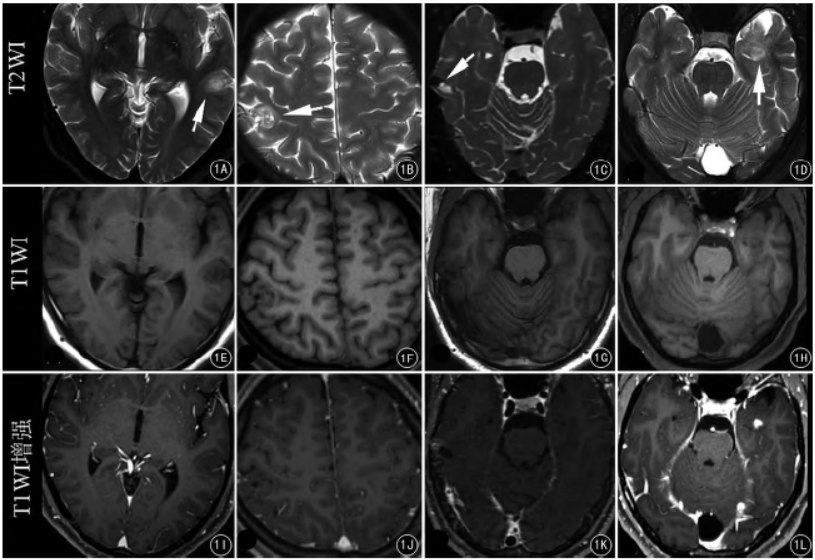

图1A ~ L 4 例PLNTY 病灶( 白箭) 在轴位T2WI( A ~ D) 、T1WI 平扫( E ~ H) 和T1WI 增强( I ~ L) 图像上不同表现。轴位T2WI 上见" 椒盐征"( A、B) 、囊变( C) ,轴位T1WI 上均为低信号,轴位T1WI 增强图像上表现为无强化或不同程度不均匀强化

4 例病灶位于颞叶( 左侧颞叶3 例,右侧颞叶1 例) ,1 例病灶位于右侧顶叶。病灶最大径1.1 ~ 3.7 cm,平均直径约1.76 cm。“椒盐征”、钙化和不同程度强化为主要特点( 图1) 。病例2~ 5 均未见扩散受限。MRS 示病例3、5 局部NAA 峰稍降低,Cho 峰稍增高,DTI 示病例3、5 病灶局部纤维束中断,病例2 局部白质纤维束受压、模糊。灌注加权成像( PWI) 示病例2、3 病灶边缘CBV、CBF 增高。

病例1,男, 25 岁,发作性呼之不应伴抽搐3 年。左侧颞叶皮层下结节,大小约1.1 cm × 1.0 cm,T1WI 呈低信号,T2WI 见“椒盐征”,FLAIR 呈混杂高信号,增强未见强化,边界清楚,周围脑实质无水肿。病例2,女, 23 岁,反复发作性抽搐12 年。右侧顶叶混杂长T1、长T2信号结节,T2WI 见“椒盐征”,FLAIR 呈混杂高信号,大小约1.7 cm × 1.5 cm,无扩散受限,增强后无明显强化,边缘模糊,局部灰质结构紊乱。MRS 未见明显异常。SWI 未见顺磁性物质沉积,内见血管信号。PWI 示CBV、CBF 升高。DTI 示局部受累脑回白质纤维束受压、模糊。

病例4,男, 26 岁,发作性愣神5 年。右侧颞叶类圆形结节,稍长T1、短T2信号、FLAIR 呈中间低边缘高信号,大小约1.1 cm × 1.1 cm,病灶左后缘见囊变,边界清,增强后不均匀强化,无扩散受限。